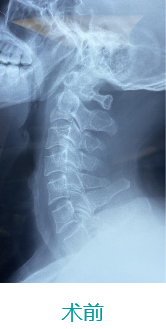

基本情形:患者男,49岁,枢椎骨折